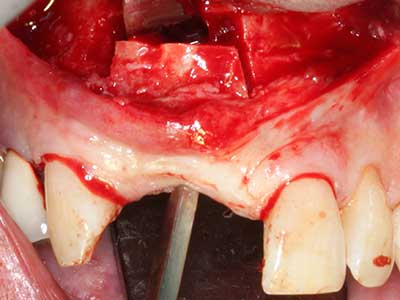

En la extracción de bloques óseos la piezocirugía también presenta ventajas adicionales: Además de la alta precisión en la osteotomía que ya se ha descrito antes, se ha comprobado que el uso de los delgados insertos de sierra resulta especialmente cuidadosas con el hueso. Frente a esto, sobre todo cuando se usan las fresas de Lindemann, cabe esperar pérdidas en la extracción significativamente más altas debido al mayor grosor de la parte frontal del cabezal (Lakshmiganthan, Gokulanathan et al. 2012). La separación basal que se necesita en particular en los injertos de bloque extraídos de forma retromolar se ve facilitada mediante sierras perpendiculares especialmente previstas a tal fin, lo que permite considerar que la cirugía piezoeléctrica es un procedimiento preciso y seguro para la obtención de bloques de hueso en el área retromolar (Happe 2007) (fig. 1-12).

Fig. 1: Preparación de una tapa ósea conforme con Piezomed (W&H, Salzburgo, Austria)

Fig. 2: Defecto del maxilar superior lateral vertical y horizontal con línea de la sonrisa alta, con indicación para la reconstrucción antes del implante.

Fig. 3: La separación basal del bloque se ve facilitada con piezas dotadas de una angulación especial.

Fig. 4: Con la rasqueta ósea se obtienen virutas adicionales de hueso autógeno.